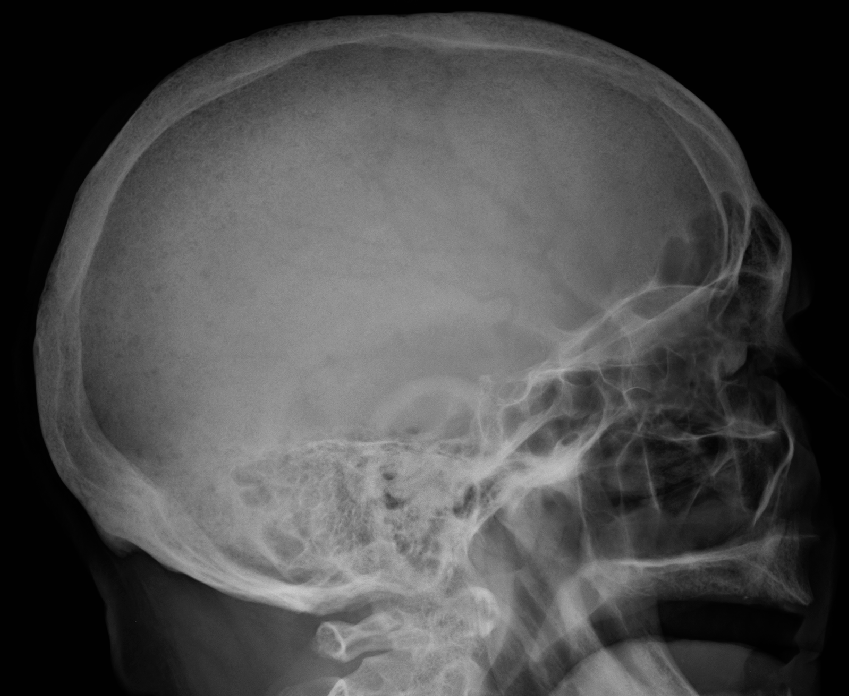

Το πολλαπλό μυέλωμα μπορεί να ανιχνευθεί κατά τη διάρκεια μιας αιματολογικής εξέτασης ρουτίνας, ωστόσο το πιθανότερο είναι να διαγνωσθεί μόνο μετά από ακτινογραφίες οστών λόγω καταγμάτων ή γιατί οι ασθενείς παρουσιάζουν άλλα συμπτώματα. Τα συμπτώματα είναι δυνατό να ποικίλουν από άτομο σε άτομο. Ορισμένοι άνθρωποι δεν παρουσιάζουν συμπτώματα κατά τη διάρκεια των πρώιμων σταδίων της νόσου. Κοινά συμπτώματα περιλαμβάνουν:

– Μαγνητική τομογραφία ή ακτινογραφίες για τον έλεγχο πιθανής λέπτυνσης των οστών ή καταγμάτων